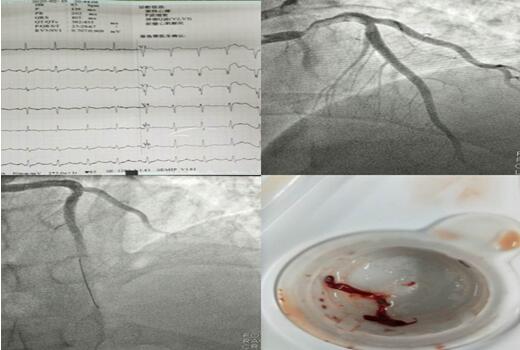

2月10日00:10,患者張某,50歲男性,突發胸痛2小時,悶痛,位于胸骨后……;

2月15日21:00,患者劉某,56歲女性,突發胸痛4小時,位于心前區,呈絞榨樣疼痛……;

2月20日20:40,患者魚某,46歲男性,突發胸痛6小時,位于心前區,呈絞榨樣疼痛……;

3個夜晚,3段急促的電話鈴聲打破了夜的寂靜,電話另一端傳來家屬的焦急與擔心。在接到胸痛中心電話的第一時間,3個夜晚的值班醫生立即進行各項準備,通知當班護士備好讓搶救物品及藥品。患者被送達到科室同時啟動導管室,進行術前相關檢查,明確手術指征、與患者家屬談話說明病情。 3個不同的夜晚,無影燈下卻站著同樣的2個人,崔旭輝主任與張洪亮醫生正在爭分奪秒的搶救患者的生命。他們為其中兩名患者進行了支架植入術,為另一名患者抽吸出血栓。術后3名患者生命體征均平穩,癥狀較前緩解。

2月11日,患者毛某行CRT-D術,該患者是一位69歲的男性,因勞力性胸悶、氣短入院,多次因心衰于當地醫院住院治療,因疫情影響,輾轉來到我院,入院后行冠脈造影提示正常,結合心臟超聲,診斷為擴張型心肌病,給予強心、利尿、擴冠后心衰糾正但不明顯。崔旭輝主任指出:該患者左室射血分數降低(LVEF28%),NYHA心功能Ⅳ級,左束支傳導阻滯,QRS增寬大于120ms,有行CRT-D指征,即通過雙心室起搏器同步刺激左、右心室再同步化治療及埋置性心臟除顫器以改善心功能、治療惡性心律失常。術后患者QRS波群時限縮短、癥狀明顯改善。患者出院當天,科室收到來自患者家屬的感謝信,這份感謝信是對我們最好的禮物,是對我們工作的肯定和贊許。